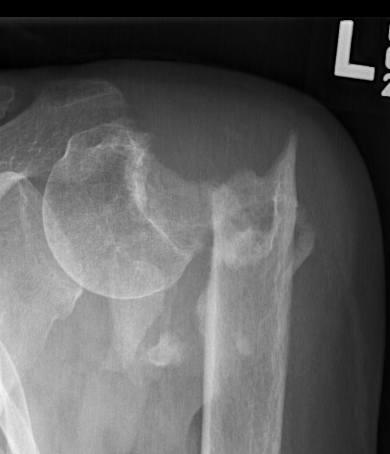

Severe comminuted proximal humerus fractures

100% displaced / off ended

Fracture - dislocations

- comminuted, 3 or 4 part

- head spltting fracture

- off ended / 100% displaced

Unreconstructable fracture - 4 part, comminuted, head spltting fracture